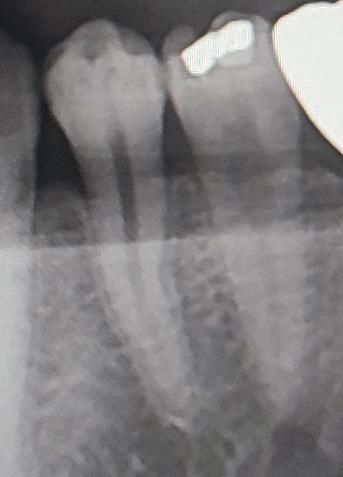

• 2번 째 사진

엑스레이상에서 별다른 문제점이 있어보이진 않습니다 잇몸과 관련하여 잇몸치료, 항생제 처치등 해주고 좀 더 지켜봐야할것 같습니다